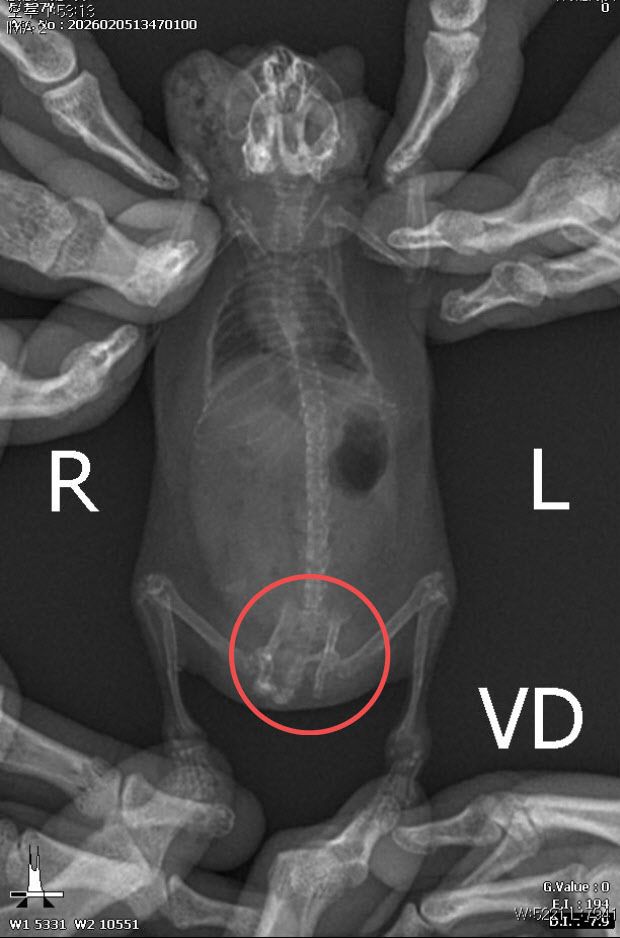

이어 “귀가 찢어지는 등 다수의 개체에서 교상 흔적이 관찰됐으며 일부 개체는 장기간 반복된 타박상으로 인해 골절 및 재골절이 의심되는 정황까지 확인됐다”고 덧붙였다.